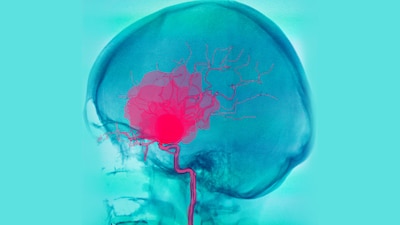

Pero aunque puede ser un proceso normal y esencial, si un coágulo se desprende de donde se formó, puede resultar peligroso, sobre todo si se aloja en un órgano o en una arteria demasiado estrecha. Esto es lo que se conoce como un émbolo y puede bloquear el flujo sanguíneo arterial, que es esencial para los órganos vitales y puede derivar en una embolia pulmonar (coágulo de sangre en los pulmones), un accidente cerebrovascular isquémico (coágulo en el cerebro) o un ataque cardíaco. También puede bloquear las venas, como una trombosis venosa profunda en las piernas, conocida como trombo.

Esto se debe a que el virus SARS-CoV-2 ataca las células endoteliales que recubren los vasos sanguíneos, lo que provoca un aumento de los coágulos en todo el cuerpo y se presenta como una enfermedad vascular.